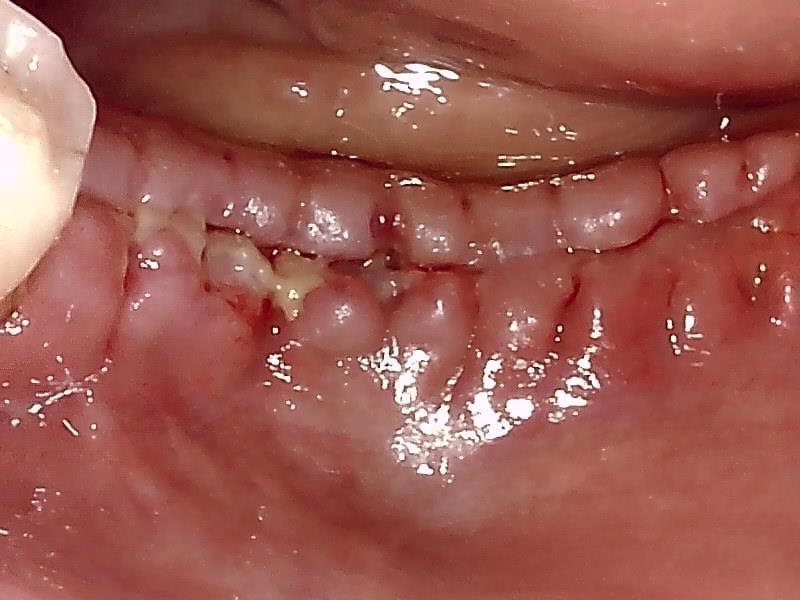

減張切開した歯肉を縫合した状態です。

抜糸した状態です。